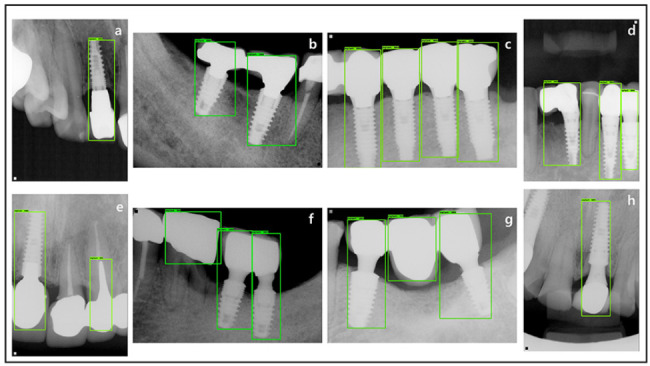

Various results of the running implant detection inference against the test dataset were obtained based on the trained detection model. The results showed TP = 124, FP = 3, and FN = 1 among all 125 ground truth labels, including all the dental implants and peri-implant tissue within the whole test dataset. Considering the FP and FN, the FN did not detect the implant profile that was truncated in the corner of the image. If all the profiles of the implant had been obtained clearly on the periapical radiograph, a higher accuracy would be anticipated. Meanwhile, FP occurred when brightness and saturation within the image were similar to those of implants such as crowns, pontics, and screw posts and crowns (Fig. 5).

Fig. 5.

Example images of the result of the implant detection test. a–d: True positive (TP) cases that detect dental implants and peri-implant tissue well, e–g : False positive (FP) cases, h: false negative (FN) case